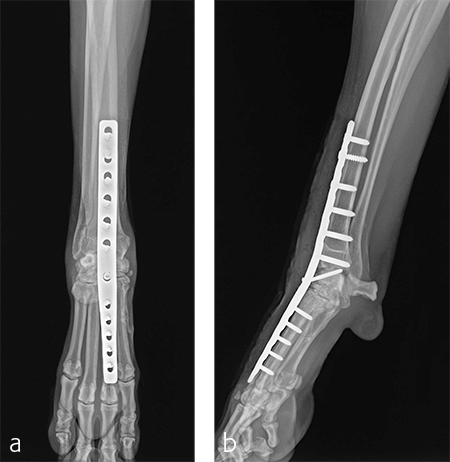

A 2.7/3.5 Pancarpal Arthrodesis was applied to the dorsal aspect of the carpus using a combination of locking and cortical screws. A 2.7 mm cortical screw was used to attach the plate to the radiocarpal bone. Five 2.7 mm locking screws were used to attach the plate to the 3rd metacarpal bone. Five 3.5 mm locking screws and one 3.5 mm cortical screw were used to attach the plate to the dorsal surface of the radius. A combination of locking and cortical screws was used to provide compression (cortical screw placed in eccentric position to provide compression across the radiocarpal joint) and achieve excellent stability and limb alignment. The incision was closed in routine fashion.

Postoperative radiographs revealed proper joint orientation and compression of the multiple antebrachiocarpal joint levels (Fig 5). Implant placement was considered excellent.